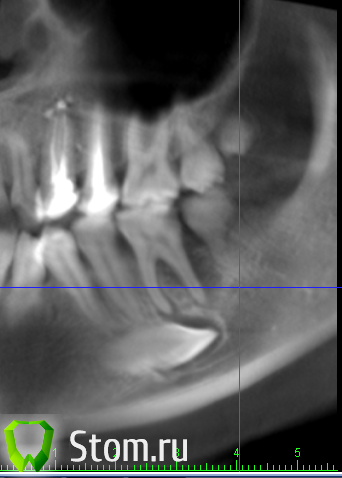

Елена *** Опубликовано 13 апреля, 2012 Автор Поделиться Опубликовано 13 апреля, 2012 Этот снимок сделать еще до того как раскрыли зуб.Сегодня звонила хирургу - он сказал , что зуб раскрыли, чтобы выходил гной. Сказал прикладывать к шишке мазь левомиколь. А на сколько ее надо прикладывать? Ссылка на комментарий